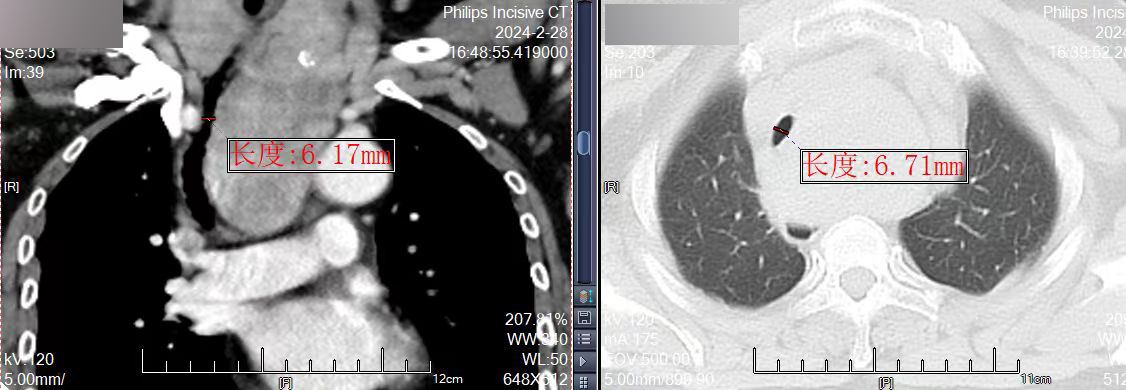

不久前,许阿姨出现活动后气促的情况,在当地医院检查后发现巨大甲状腺肿物,颈部肿大的甲状腺沿着气管向胸腔内生长,到达气管隆突水平,呈现“哑铃”状,在胸骨后将气管压迫移位、弯曲迂回,管腔受压变窄,最窄处仅为6mm,为“困难气道”。而正常成人气管直径约15mm-20mm,直径<8mm既可发生呼吸困难,这也就解释了为什么许阿姨会在活动后出现气促。

巨大胸骨后甲状腺肿致气管变形狭窄

气管最狭窄处仅6mm